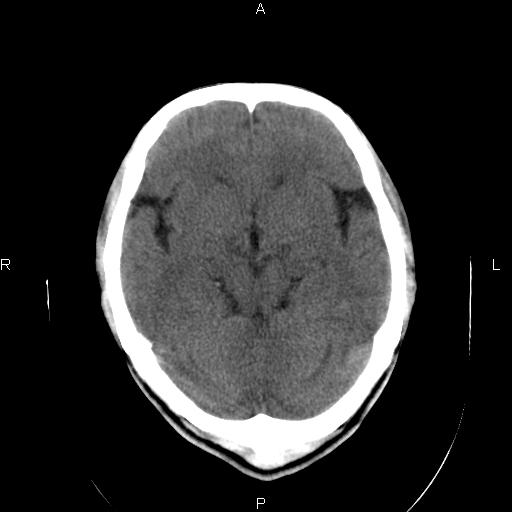

男性,40岁,反复头痛,视物旋转一月余,无呕吐,pe未见明确异常。

我的问题是上矢状窦高密度怎么解释?请各位专家不吝指教,谢谢!

可结合增强或mrv检查除外上矢状窦血栓。

颅脑ct轴位平扫颅内未见明确异常;建议必要时行mri检查。